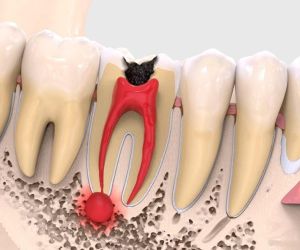

Лечение каналов зуба

Лечение каналов зуба предполагает сохранение и восстановление зуба, пораженного инфекцией или другим патологическим процессом. Основная зад…

Лечение пульпита